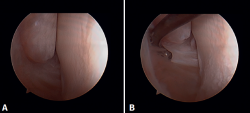

Arthroscopic evaluation of the syndesmosis

From the anteromedial portal we can directly visualize the distal fibers of the ATFL. Disinsertion of these fibers does not always result in instability of the syndesmosis, but it does require us to check it. In our experience, we prefer assessment of the coronal plane of the syndesmosis. We introduce the arthroscope into the tibiotalar joint directing the camera cranially. In this way we have a direct view of the distal tibiofibular joint. We then assess stability by attempting to insert the palpation probe into the joint. If it is possible to do so, we classify the syndesmosis injury as unstable (Figure 6A).

Arthroscopic evaluation of the deltoid ligament

There are multiple methods for assessing instability of the medial complex; using the anterior ankle portals it is possible to assess the stability of the deltoid ligament in its main plane of action, corresponding to the coronal plane. Chun et al.(20) described instability when it is possible to introduce an arthroscopic palpation probe into the medial tibiotalar space (Figure 6B). Vega et al.(21) reported that, in the majority of injuries, the most anterior portion of the deltoid ligament is detached from the medial malleolus, while its proximal insertions remain intact. In this situation, the arthroscopic palpation probe can be inserted between the medial wall of the internal malleolus and the deep fibers of the deltoid ligament.

Figure 5. A: anterior view of the medial recess of the ankle; B: the fibers of the deep tibiotalar ligament are tightened with the palpation probe.

Figure 6. Maneuvers to demonstrate ligament instability. A: lesion of the syndesmosis allowing insertion of the palpation probe into the distal tibiofibular zone; B: lesion of the deltoid ligament allowing insertion of the probe into the medial tibiotalar space.